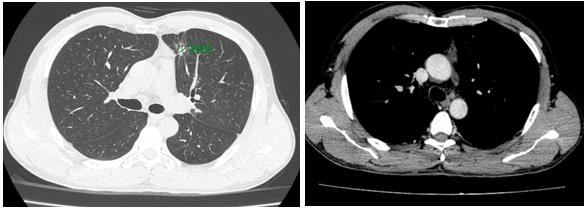

-         Cắt lớp vi tính lồng ngực:

Sau 3 tháng điều trị đích:

U nguyên phát và u thứ phát ở cả 2 phổi đều giảm kích thước rất nhiều, không thấy hạch trung thất.

Sau 6 tháng điều trị:

U nguyên phát chỉ còn kích thước rất nhỏ, u thứ phát 2 bên phổi đã mất hết.